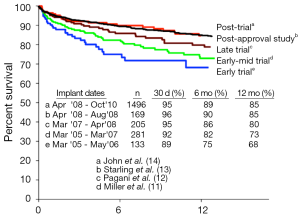

Following the US Food and Drug Administration’s (FDA) approval of the Thoratec Heartmate II CF-LVAD as a BTT in 2008, improvements in survival have continued to increase. One year survival from the initial 133 patients reported by Miller et al. in 2007 was 68% (11). By 2009, this number had climbed to 73% one year survival (12), and by 2011, the one year survival reported by INTERMACS from the postapproval study had climbed to 85% (13) (see Figure 3). Most importantly, patients with CF-LVADs were noted to have improved survival compared with patients supported by pulsatile flow devices (15).

More recently, CF-LVAD outcomes have continued to improve as our collective experience implantation and post-operative care has grown (Table 1). A retrospective multi-center analysis comparing patients implanted with a Heartmate II LVAD after FDA approval in commercial use with the results from the clinical trial reported a consistent improvement in outcomes (14), with an increase in the percentage of patients who were either transplanted, explanted, or receiving ongoing LVAD support at 6 months and 1 year in the posttrial cohort. Similarly, recently reported figures from patients implanted with the HVAD have also shown remarkable improvements in outcomes, with survival now exceeding 90% at 1 year (31). In fact, the increased utilization of CF-LVADs, along with their excellent long-term outcomes, have led to a decrease in the number of patients transplanted in the first year, from 48% during the Heartmate II BTT clinical trial to only 39% during the post-trial period (14). In this same period, one year survival on the heart transplant waiting list actually increased despite the decreased transplantation rate. This indicates an increase in the number and proportion of patients awaiting heart transplantation after LVAD implantation, further highlighting the feasibility and reliability of extended LVAD support.